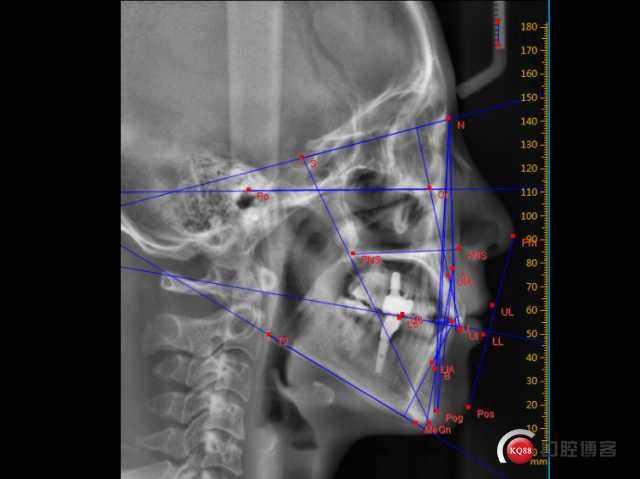

她后来到了医院,医生给的方案就是隐形矫正。你可能会想,这么严重,隐形牙套那薄薄的塑料片,能行吗?这就是技术的关键了。医生通过数字化手段,为她精准设计了一步一步的移动方案,做了60多副牙套,花了两年多时间,硬是把那过度前突的牙槽骨和牙齿,给“劝”了回去-2。看到最后矫正效果的小宁,终于敢开怀大笑了-2。这个过程里,对于如何高效、健康地控制牙齿移动,特别是把前牙往后收的同时避免副作用,医生们就有讲究了,这里头可能就用到了我们今天要说的核心——隐形矫正蛙跳技术。

在隐形矫正开始前,医生会通过口扫获取你牙齿的3D模型,在电脑里进行完整的治疗模拟-3。每一副牙套、牙齿每一步要移动0.25毫米还是0.5毫米、往哪个方向偏转几度,都是提前设计好的-10。对于隐形矫正蛙跳技术而言,这意味着医生可以在虚拟空间中,提前演练整个“接力”过程:下前磨牙作为支抗牙需要多稳固?传递给下前牙的压低力值多大最合适?如何通过附件(牙套上的小凸起)来增强控制?这些都能做到“心中有数,眼里有图”-10。

而且,隐形牙套是包裹住整个牙冠的,它能提供传统钢丝难以实现的、从各个方向上的控制力-10。这对于在压低牙齿时,防止牙齿在移动过程中发生不必要的唇倾或舌倾,保持牙根也在正确轨迹上移动(即“控根移动”),特别有帮助-10。相当于给每颗牙穿上了量身定做的“紧身衣”,引导它沿着设定好的路径,稳稳地“走”到终点。